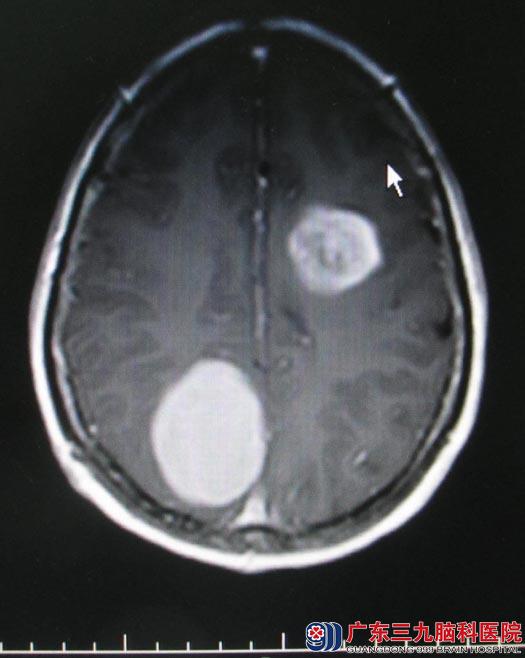

广东三九脑科医院头颅MRI检查结果:右侧顶部镰旁占位病变,呈明显高灌注,MRS支持脑外病变,内示细小血管,考虑脑膜瘤可能,待排血管外皮细胞瘤;左侧放射冠-半卵圆中心、左侧额叶多发异常信号影,局部存在多发高灌注区,NAA峰明显下降,Cho峰明显升高,SWI示病变内可见微量出血,考虑偏恶性肿瘤性病变,以间变性星形细胞瘤可能性大。

神经外五科鲁明主任阅片后解析:头颅MR所示右侧顶部镰旁占位及左侧额叶占位,右侧顶部镰旁占位考虑脑膜瘤可能,而左侧额叶占位考虑恶性肿瘤,两个肿瘤体积均较大,占位效应明显,均有手术指征,可考虑一次性手术切除。其中右顶部肿瘤侵犯上矢状窦,术中需要注意静脉窦的保护,避免静脉窦闭塞导致静脉回流障碍;左侧额叶肿瘤临近大脑语言及肢体运动中枢,术中需要注意保护正常脑组织,减少术后功能的损伤。